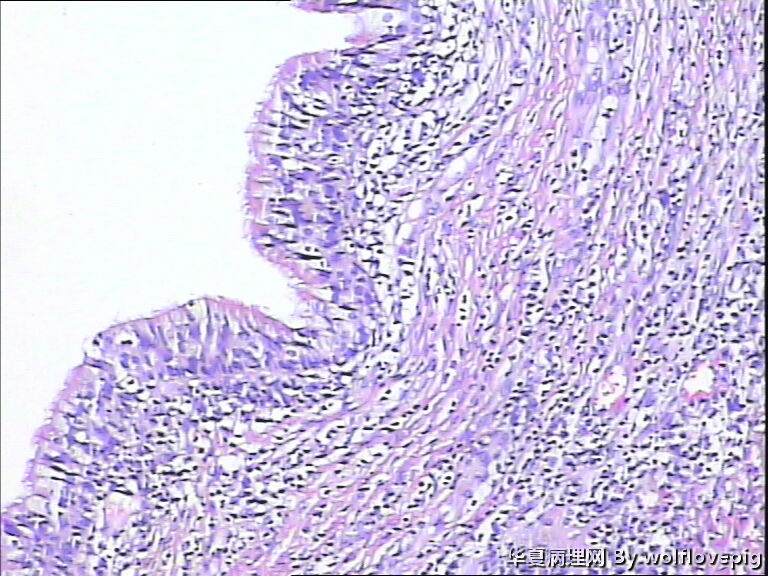

31y,阴蒂附近囊肿2.0*1.5cm

外阴最常见的囊肿是前庭大腺囊肿,囊肿一般衬以移行上皮,常伴有非角化性鳞状化生,也有的呈扁平或立方状,囊肿周边附近可以见到黏液腺体。

此例有点特殊,看到一些纤毛柱状上皮被覆,称为纤毛囊肿,属于前庭大腺囊肿的特殊改变。

前庭大腺囊肿位于外阴后半部,而此例位于阴蒂附近。

泌尿生殖窦起源的外阴囊肿(粘液性和纤毛囊肿)

1,多见于21-30及31-40的多产妇女,病变多位于外阴前庭。

2,组织学上,粘液性囊肿含有与宫颈内膜或阴道腺病一样的粘液性上皮内衬,少数情况下可出现鳞状上皮化生。也有报道有些病例出现纤毛细胞,可以与粘液上皮混合存在。